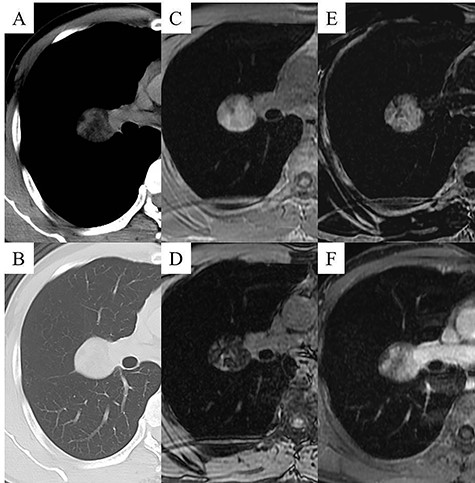

The patient was a 48-year-old man, in whom a round mass lesion was detected in the hilum of the right lung by chest radiography performed at an annual health checkup (Fig. 1A). The image of this mass lesion had been interpreted as a normal view on chest radiography performed at his annual health checkup one and a half years previously (Fig. 1B). The mass detected by radiography was also detected by computed tomography (CT), as a 3.5 cm low-attenuated mass with a circumscribed margin in a fissure of the right lung (Fig. 2A, B). On magnetic resonance imaging (MRI), this mass lesion was displayed as a high, low and low signal mass on the in-phase of T1-weighted imaging (WI), out-of-phase of T1WI and T2WI, respectively (Fig. 2C–E). The mass lesion was not clearly enhanced by fat-saturated contrast-enhanced T1WI with extracellular gadolinium contrast material (gadoterate meglumine; Magnescope®; Guerbet, Villepinte, France) (Fig. 2F). The radiological observations were highly suggestive of a hamartoma.

Chest CT images displaying the mass lesion; the low-attenuated mass was displayed in the mediastinal window (A), and the diameter of the mass was 3.5 cm and the mass was located close to the fissure of the right lung in the pulmonary window (B). Chest MRI displaying the mass lesion; the mass lesion was displayed as a high signal on in-phase T1WI (C), the mass was displayed as a low signal on out-of-phase T1WI (D), the mass was displayed as a low signal on T2WI (E), and the mass lesion was not clearly enhanced by fat-saturated contrast-enhanced T1WI with extracellular gadolinium contrast material (gadoterate meglumine; Magnescope®; Guerbet) (F).